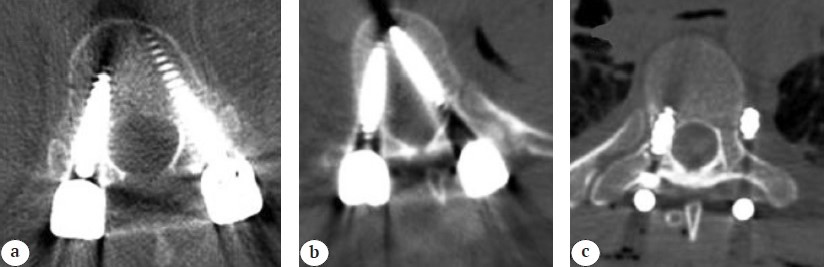

The patients underwent neurological examination in the postoperative period. They were given antibiotics, and brace was prescribed for all of them. Different techniques are used to detect breaches intraoperatively, including fluoroscopy, and postoperatively by radiography, CT, or MRI. In this study, we utilize postoperative CT scans to assess the accuracy of pedicle screw placement and intraoperative fluoroscopy to detect any apparent breaches (Figure 1).

Figure 1. Postoperative CT scans assessing the accuracy of pedicle screw placement of: a — a 35-year-old female with L1 fracture post-fixation with T12, showing screws within the pedicle; b — a 43-year-old male with T12 fracture post-fixation with T10, showing a medial breach; c — a 41-year-old female with T7 pathological fracture with T6, vertebra showing a lateral breach

The placement of the pedicle screw was assessed using postoperative CT scans. We analyze the axial, sagittal, and coronal views to get a comprehensive view of the screw trajectory, whether the screw is in the planned trajectory of the pedicle and the vertebral body and assess any cortical breach.